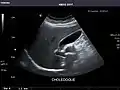

Gallbladder

Gallbladder: No stones, wall thickening, or pericholecystic fluid.

Common Bile Duct: Nondilated measuring 1.3 mm at the level of the porta hepatis.